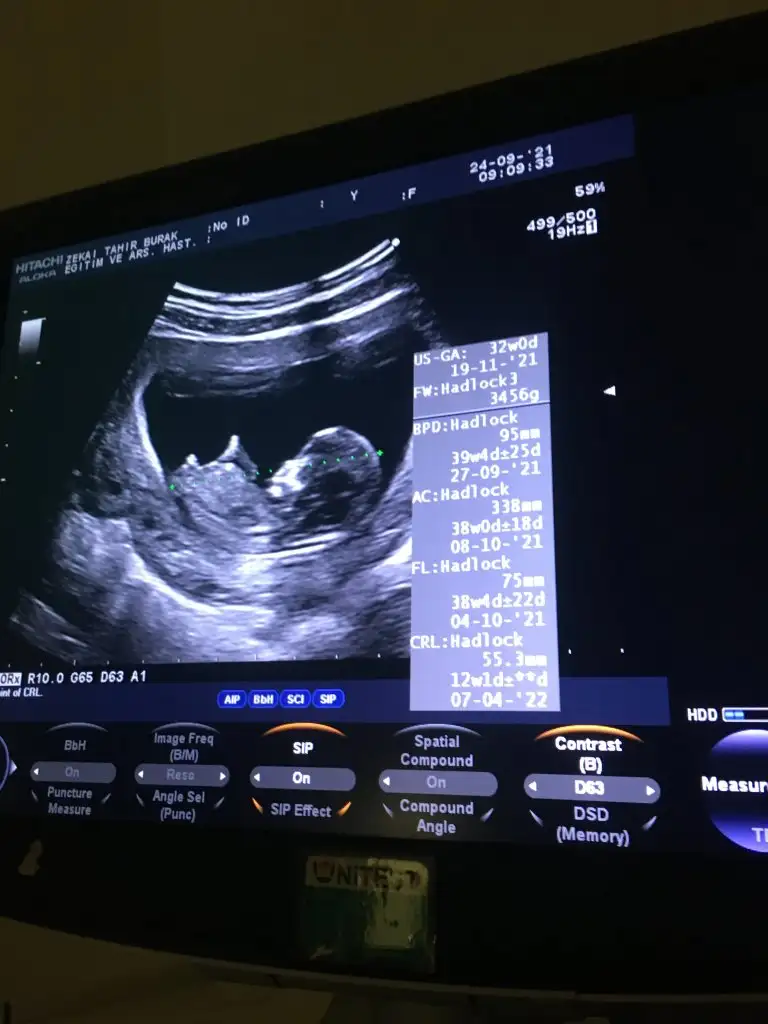

Erkek gibi sanki Emin olmadım diğerinide paylaşınKızlar merhaba. Bizde 12+2 deyiz. Sürekli hareket ettiği için en net görüntüsü bu oldu. Yorum yapabilir misiniz. Teşekkür ederim

Bir gün önceki de bu şekilde. Uyuyordu sanırımErkek gibi sanki Emin olmadım diğerinide paylaşın

Kiz gibi geldiBir gün önceki de bu şekilde. Uyuyordu sanırım